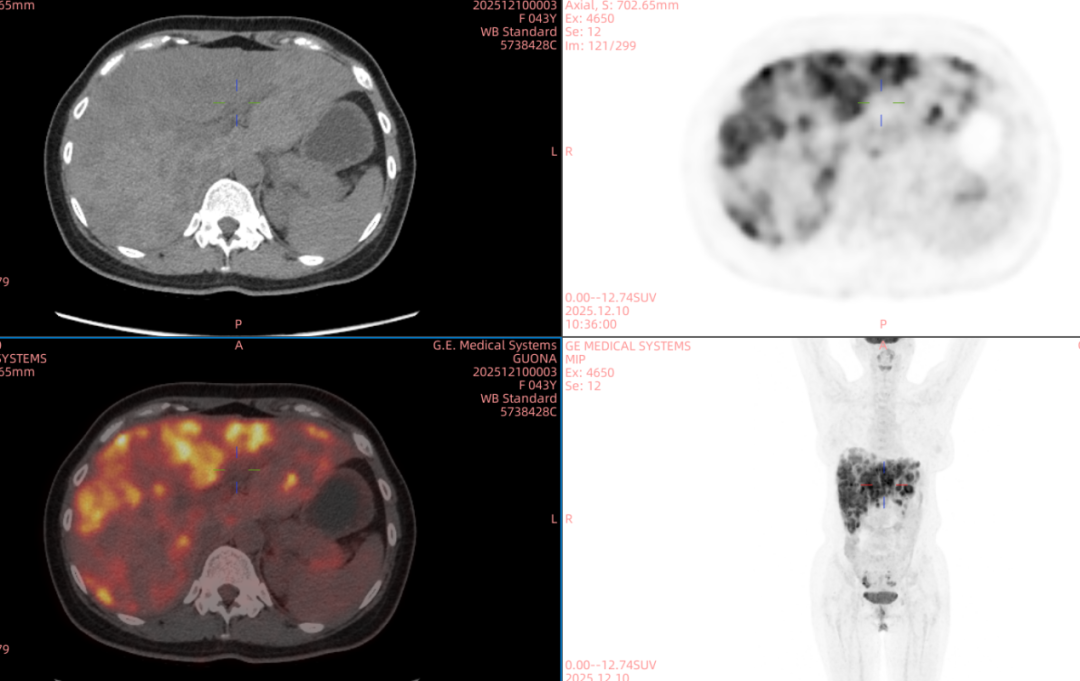

近日,甘肃省武威肿瘤医院武威重离子中心再迎新突破——全球首创双布拉格加重离子晶格放疗技术正式应用临床。

“双布拉格”,并非指代两个物理峰值,而是两大核心治疗理念的深度碰撞与融合。第一个“布拉格”,是物理学范畴的布拉格峰——重离子束流可在体内特定深度释放绝大部分能量,这一特性构筑起“指哪打哪”、极致保护正常组织的物理基石。第二个“布拉格”,是免疫学范畴的布拉格治疗,即国际前沿的PRaG协同治疗方案。它通过精准放疗在局部“点火”,释放肿瘤抗原;以GM-CSF为“导航”,引导免疫系统识别肿瘤细胞;再借助PD-1抑制剂“解除免疫刹车”,让免疫细胞能够持久、全身性地攻击肿瘤,最终追求珍贵的“远隔效应”。而晶格放疗,正是连接两大“布拉格”理念的关键桥梁。针对常规手段无法照射的巨大肿瘤,它将均匀剂量场转化为无数离散的高剂量“能量岛屿”。这种模式不仅能奇迹般保护穿插其中的正常组织与脉管结构,其独特的剂量分布,更被证实可高效诱发免疫原性细胞死亡,将物理打击的能量,转化为激活全身免疫反应的“信号”,让肿瘤的局部治疗与全身控制成为现实。

四大优势协同发力:一,依托重离子射线特有的“布拉格峰”物理特性,实现对深部肿瘤的“定点爆破”;二,采用“晶格放疗”先进布野技术,在巨大肝肿瘤内部精准布设能量“棋盘格”,在高效杀伤肿瘤细胞的同时,为残存正常肝组织与关键脉管留存生存空间;三,将此次精准物理打击,完美嵌入“布拉格治疗”免疫协同策略,以此作为激活全身免疫反应的“点火器”,联合PD-1抑制剂与GM-CSF,力求激发远隔效应,对未被照射的病灶形成攻击;四,引入干细胞支持下的新一代免疫细胞疗法,整合诱导多能干细胞(iPSCs)或间充质干细胞(MSCs)来源的免疫效应细胞(如CAR-T、CAR-NK和TCR-T细胞)与工程化技术,显著提升癌症免疫治疗的可及性与疗效。